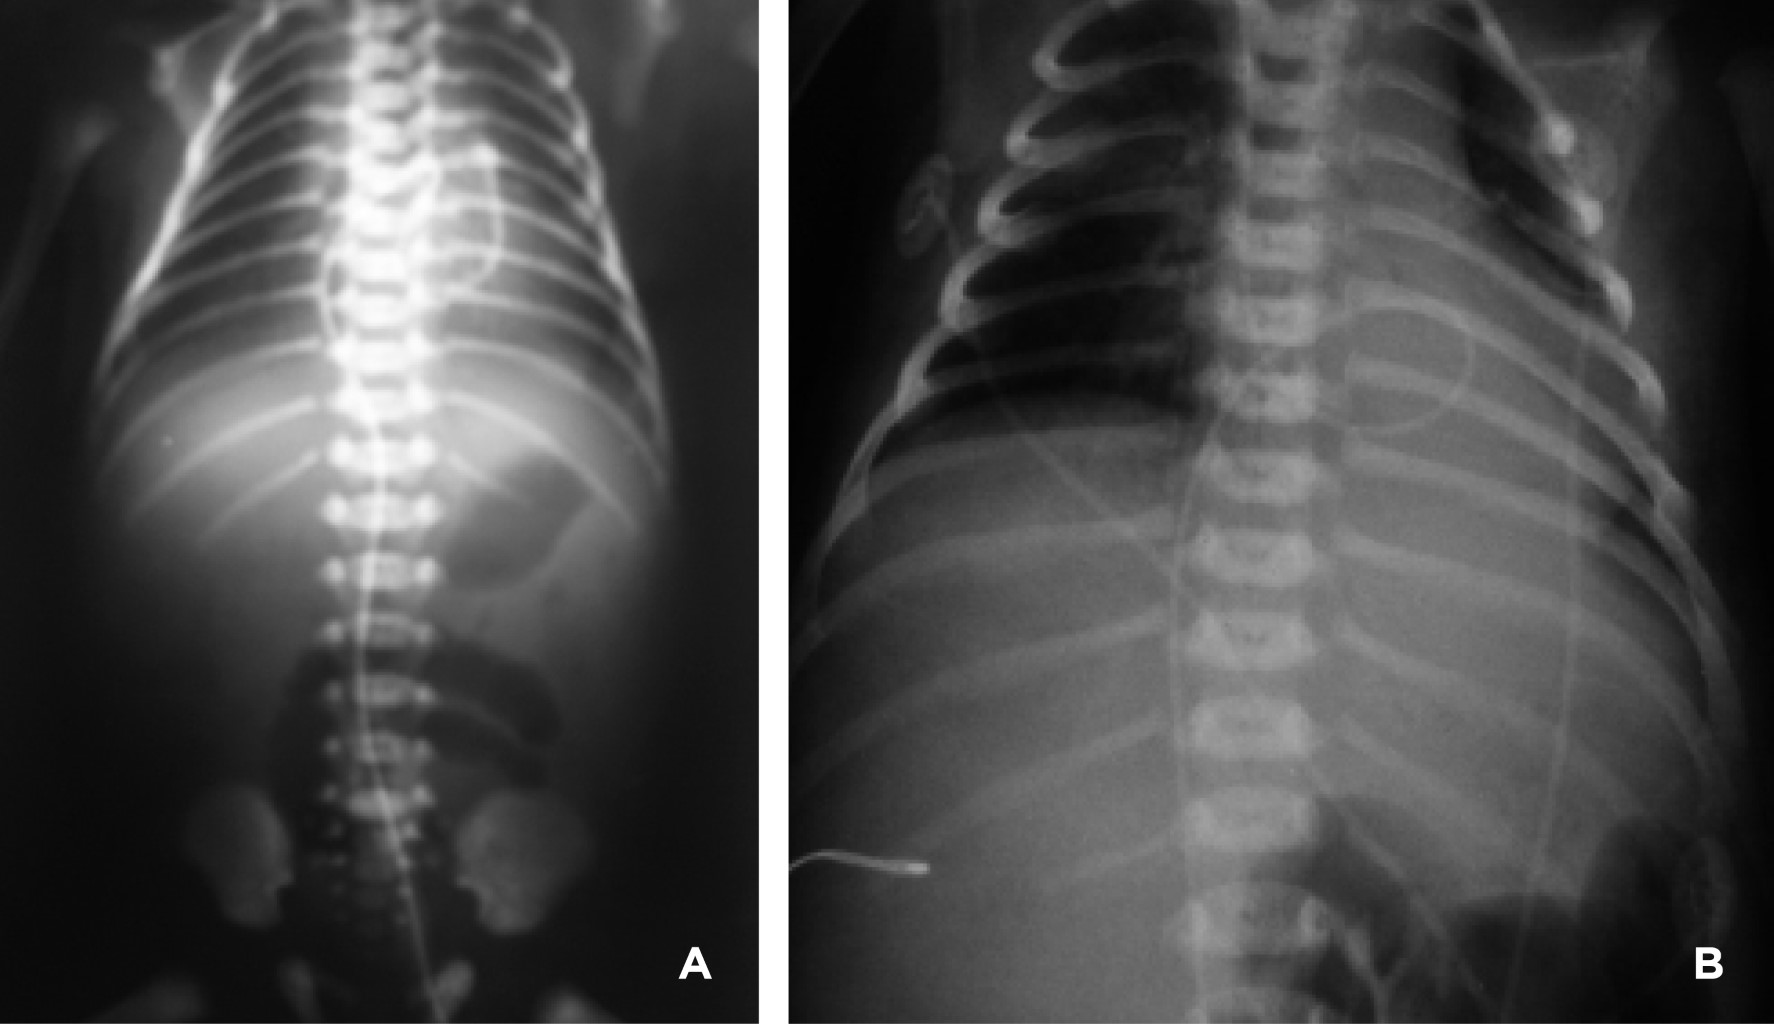

Catéter arterial. La punta del catéter arterial tiene dos posiciones correctas: alta y baja. La posición alta radiológicamente debe quedar entre las vértebras (dorsales o torácicas) D6-9; mientras que la baja entre las vértebras (lumbares) L3-4. De esta manera, se evita la zona peligrosa que queda en el espacio comprendido entre la vértebra dorsal 10 y la vértebra lumbar 2. Esta zona peligrosa comprende el nacimiento de grandes troncos arteriales (tronco celíaco situado en D11, arteria mesentérica superior en D12-L1, arteria renal izquierda y derecha en L1-L2, arterias vertebrales dorsales y lumbares, arteria mesentérica inferior en L3 y bifurcación de la aorta en L4) que deben ser evitados por la posibilidad de provocar la liberación de émbolos o momentos de isquemia que condicionen la aparición de daño renal, intestinal, de médula espinal o de extremidades inferiores (Figuras 7 y 8).2

• 2. La trombosis asociada a catéter venoso puede causar obstrucción del sistema venoso hepático, provocando trombosis portal, cuya complicación más tardía (se puede manifestar hasta 10 años después) es la hipertensión portal o síndrome de Budd-Chiari. En relación al catéter arterial la complicación más temible es la trombosis, que se presenta desde 9 a 28%, y la complicación más frecuente es la hipertensión arterial sistémica, provocada por estenosis de la arteria renal como consecuencia de la colocación incorrecta del catéter cerca de las arterias renales, pudiendo llegar a provocar en recién nacidos prematuros hemorragia intraventricular. No se ha demostrado que la posición alta o baja del catéter arterial incida sobre la frecuencia de trombosis, por lo que teniendo en cuenta este hecho, es más práctico dejar el catéter en posición alta, ya que en esta forma existe un mayor margen entre las distancias adecuadas; además, en caso de quedar en posición anómala, zona peligrosa, se puede retirar parcialmente a la posición baja. Debemos tener presente que nunca se podrá avanzar un catéter arterial o venoso que esté mal posicionado después de instalado.3,9,12

• 8. Vasoespasmo arterial. Cuando el catéter arterial se deja en posición baja anómala puede presentar cambios de coloración de las extremidades inferiores (Figura 18), glúteos o ambos, consistentes en general por blanqueamientos transitorios. Cuando ello ocurre la conducta es calentar la pierna contralateral, con una compresa tibia, intentando producir vasodilatación refleja y si en un plazo de 15 minutos el fenómeno persiste, el catéter debe ser retirado, ya que se reporta incluso pérdida de la extremidad. Si a pesar de retirarlo persisten datos de isquemia, utilizar fibrinolíticos, vasodilatadores o heparinización.3,5 El catéter arterial en posición alta anómala se puede asociar a hipertensión arterial, isquemia renal (insuficiencia renal), hipoglucemia refractaria (punta del catéter en arteria celiaca), isquemia mesentérica (enterocolitis necrosante), isquemia de médula espinal e isquemia de extremidades inferiores.4 Otras complicaciones del catéter arterial descritas son falsos aneurismas, embolismos aéreos y de gelatina de Wharton y rotura de la vejiga.